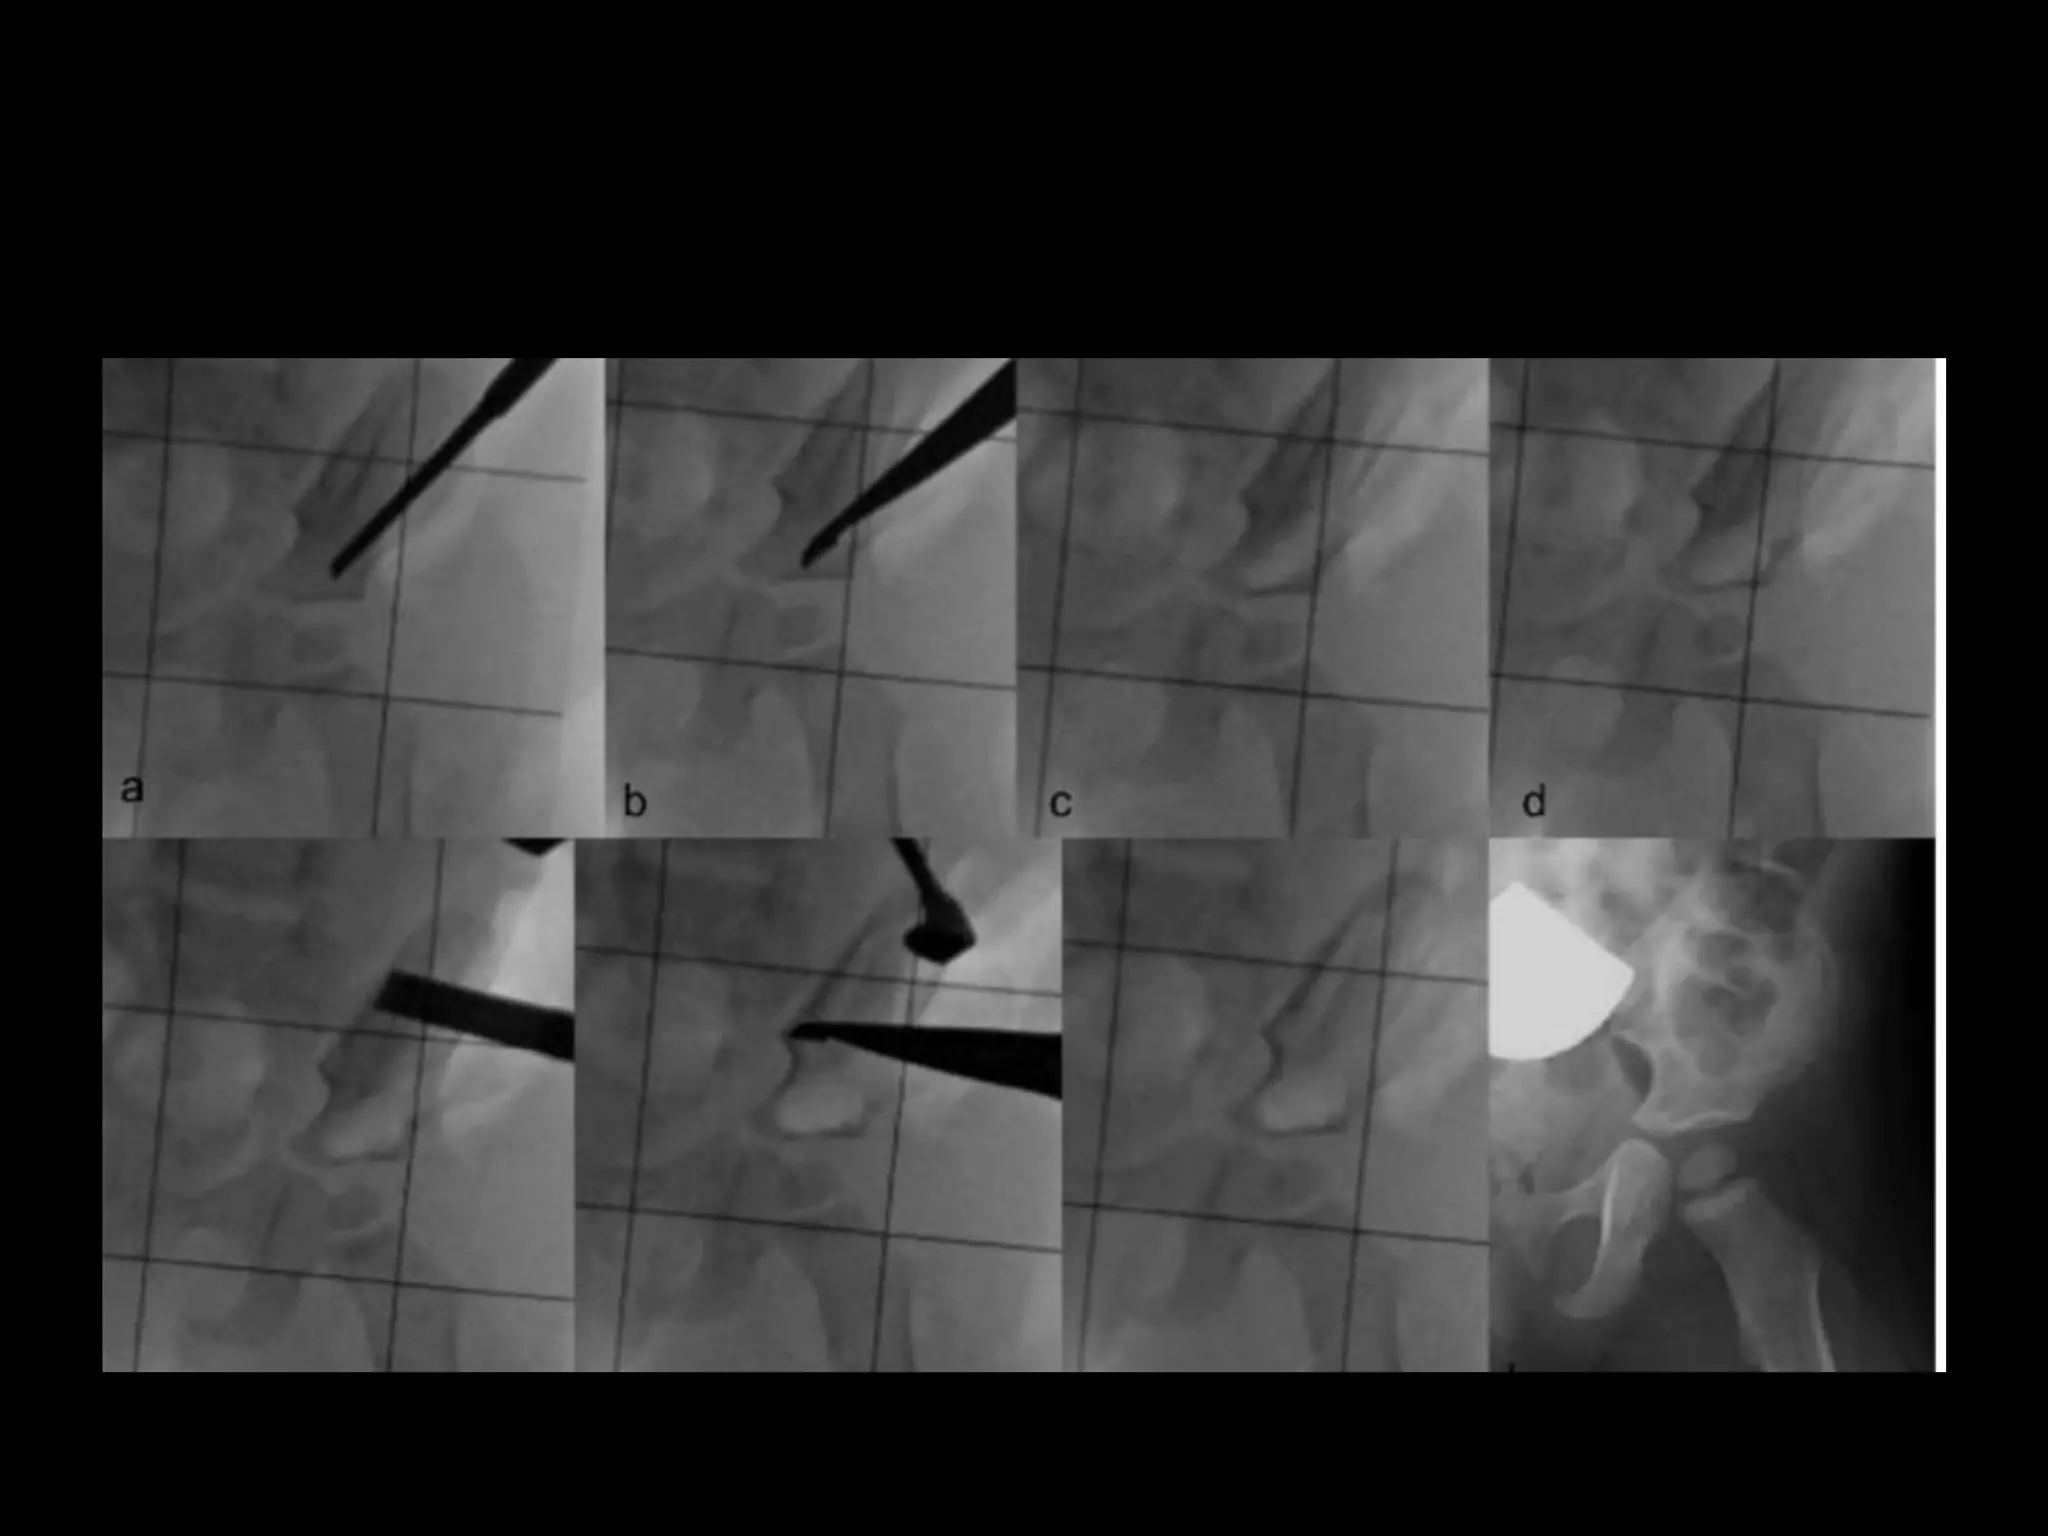

Case series

Good union

Case 2

Dec 5,2016